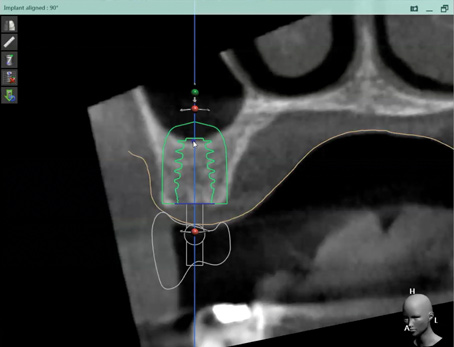

Fig 12. Virtual planning of a posterior implant (Fig 12) resulted in inadequate restorative running room for the crown emergence profile in the cross-sectional CBCT image. Revision (Fig 13) resulted in deeper positioning of the implant for restorative running room but necessitated transcrestal sinus elevation, possibly with the addition of bone via the osteotomy to tent the membrane.

Figure 12

Fig 13. Virtual planning of a posterior implant (Fig 12) resulted in inadequate restorative running room for the crown emergence profile in the cross-sectional CBCT image. Revision (Fig 13) resulted in deeper positioning of the implant for restorative running room but necessitated transcrestal sinus elevation, possibly with the addition of bone via the osteotomy to tent the membrane.

Figure 13

The direct impact of this collaborative approach is that the team is better able to anticipate surgical challenges and preplanned solutions. For instance, whether bone grafting relative to implant placement will be required and how to achieve these augmentation goals can be anticipated (Figure 12 and Figure 13). Planning implant position from the restoration down may allow positioning implants for screw retention or angled-screw technology, thus minimizing the need for cemented restorations. This type of preview may influence the choice of implant for the desired restoration, as not all systems currently offer corrective screw technologies without migrating into the use of non-authentic components.